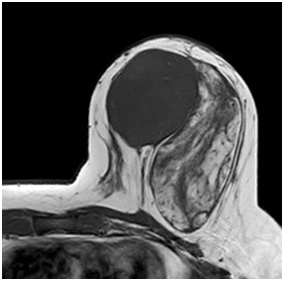

A 47year-old woman with history of a long standing palpable mass on the left breast, which was biopsied on 2006 resulting in hamartoma. She had first degree familiar history of breast cancer with her mother diagnosed younger than 50 \years of age and who later on died of that cause. The patient presented to our office, in June 2016 for progressive growth of her breast tumour. At examination her breasts were fibrous, with a palpable firm and mobile breast mass, not fixed to skin, of 8x6x5cm on the left LIQ, and another large, soft and well defined mass in left LOQ and UOQ of 10x10x5cm, There were no palpable masses in the axilla. On mammography there was a radiolucid well defined breast mass in the left LOQ and UOQ, which was stable in size and shape regarding prior mammogram of twoyears. A new dense, oval and partially defined breast mass was evident in the LIQ (Figure 1). The latter on breast ultrasound corresponded with a hypoechoic and heterogenous nodule with partially defined margins, which measured approximately 7cm. The first lesion was heterogenous and hyperechoic, measured more than 8cm, and was the previously biopsied nodule (Figure 2). She later on underwent a breast MRI that showed a round mass in the LIQ, which was hyperintense in T2, hypointense in T1, had a homogenous enhancement with a plateau curve. In the LOQ there was a well-defined mass, which was heterogenous with fibrous and fatty tissue, and did not enhance with gadolinium (Figure 3). A core biopsy of the two masses was then performed, demonstrating a biphasic fibro-epithelial lesion compatible with a PT at the LIQ, and fibrocystic changes and intraductal hyperplasia without atypia at the LOQ. On August 2016, the patient underwent a partial mastectomy, without incidents, and was sent home on the subsequent day (Figure 4). The definitive biopsy demonstrated that the tumour at the LIQ corresponded to a malignant PT (Figures 5) (Figure 6), and that the LOQ mass was a large breast hamartoma (Figures 7 & Figure 8). Posteriorly, she received 25 radiotherapy fractions, without major adverse effects. She was recently controlled with breast ultrasound and MRI that showed no residual breast lesions.

Figure 3 Preoperative breast MRI (T2 weighted image, T1 weighted image, STIR and gadolinium enhanced high resolution T1WI with fat saturation).